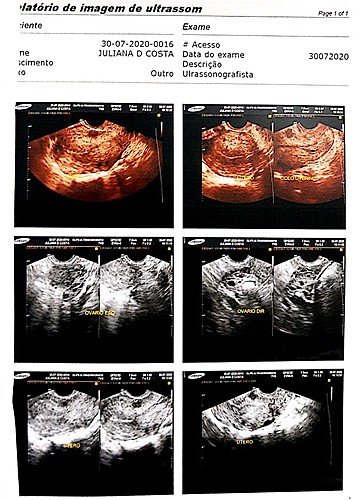

Juliana Dias da Costa de 36 anos, necessita com urgência de uma intervenção cirúrgica no útero, para a retirada de seis miomas na parede uterina. A necessidade de procedimento cirúrgico foi detectada em vários exames realizados pela paciente, que sentia muitas dores na região, o último exame realizado pela jovem, foi feito no dia 30/07/2020, onde foi feito a indicação de urgência no procedimento.